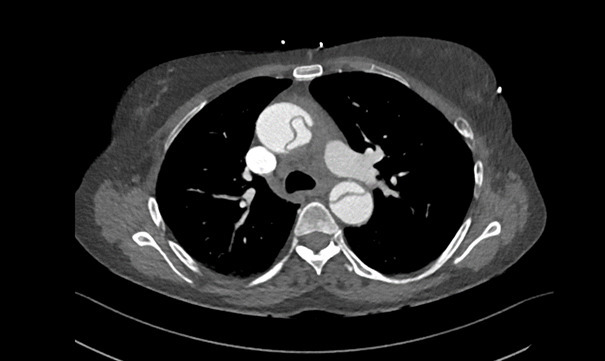

Vous recevez une patiente de 62 ans pour une douleur thoracique. Le scanner est le suivant.

Quel est votre diagnostic ?

On voit très bien sur ce temps artériel le flap intimal au niveau de l’aorte ascendante et descendante. C’est une urgence chirurgicale absolue.

On ne peut pas affirmer qu’il y a une aortite car les parois de l’aorte ne semblent pas épaissies. L’examen anatomopathologique de la pièce opératoire aura le dernier mot.

La fenêtre médiastinale ne permet pas de voir le parenchyme pulmonaire : il est donc impossible de conclure à un pneumothorax. De plus, hors contexte traumatique, il est rare, voire exceptionnel, d’avoir à la fois dissection aortique et pneumothorax.

Les artères pulmonaires ne sont pas visibles, ce n’est pas le bon moment pour éliminer une embolie pulmonaire. La concomitance des deux diagnostics est exceptionnelle.